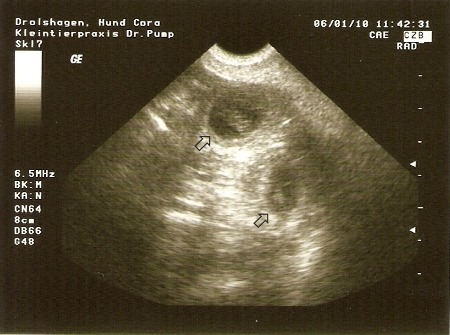

Die Mutter, Cora (Inka von Ostfriesland):